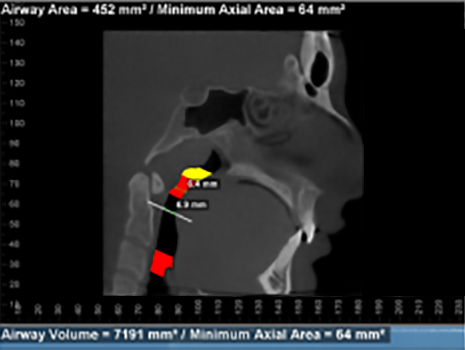

The right photo shows an improved airway during treatment. There are no black zones. Most of the airway is yellow or green. The airway behind the tongue is the most constricted as shown by the red. As we continue treatment, we will allow more room for the tongue in the mouth and increase the airway.

These show the actual airway spaces. In this view it is easy to visualize the narrowing that happens behind the tongue. When the tongue does not have adequate room in the mouth, it will have a tendency to restrict airflow and lead to mouth breathing during the day, mouth breathing while exercising, disrupted sleep cycles, daytime fatigue, headaches, TMJ and ear issues, etc.

Measurements of upper airway after 9 months.

After 9 months of treatment patient reports sleeping great, no buzzing in the ears, waking refreshed, much more energy during the day, able to bike with nasal breathing. Feels much more room for her tongue in her mouth and significantly improved ability to breathe through her nose.